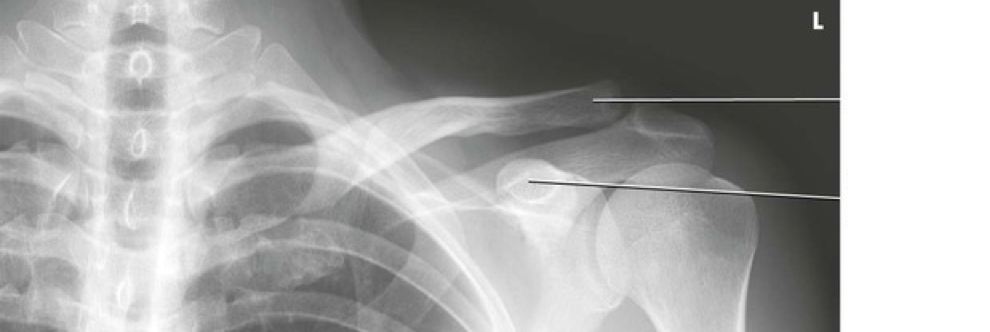

Question 2

Question

Label the image

Image:

6a2669e2-50c5-4017-a351-3cd0ba2da63d (image/png)

Answer

acromion

coracoid process

body of scapula

inferior angle

humerus